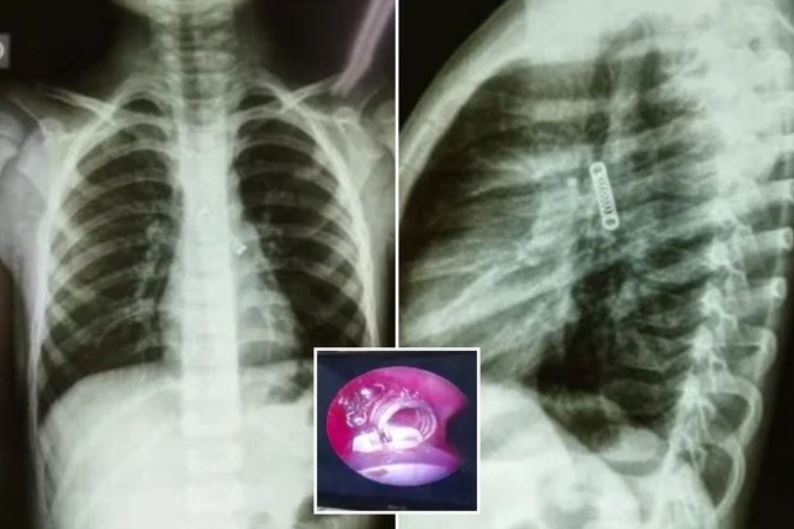

5-vjeçari kishte kollë të vazhdueshme, mjekët nuk u besojnë me çfarë gjetën në mushkërinë e tij

Prej tre muajsh kishte gëlltitur një sustë metalike e cila i kishte përfunduar më pas në mushkëri! Dhe fëmija ishte vetëm 5 vjeç.Një fëmije 5-vjeç iu hoq…